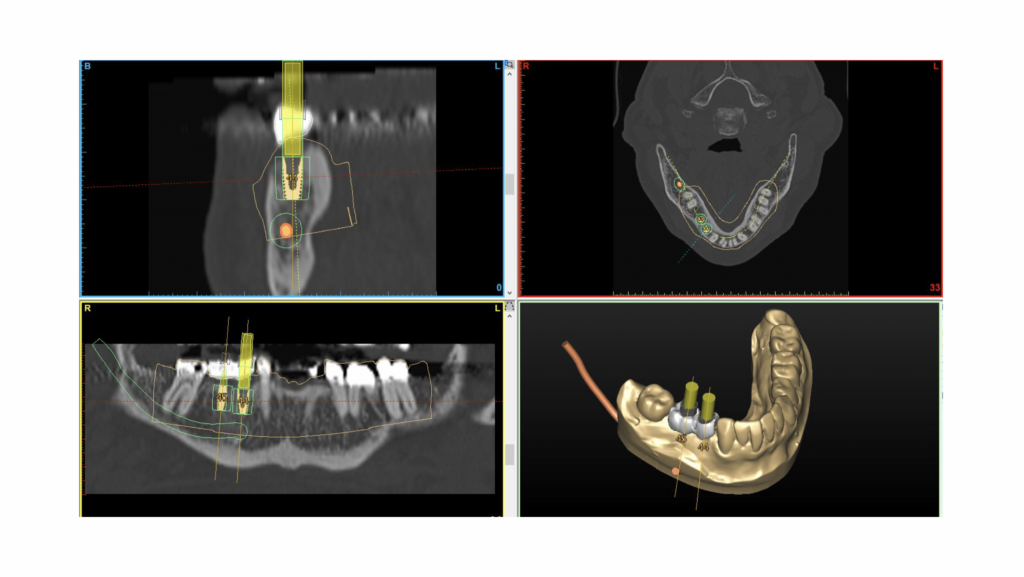

当院では、インプラント治療を行う前にCT撮影と精密検査を行い、

シムプラントという専用のシミュレーションソフトを用いて、事前に綿密な治療計画を立てています。

インプラント治療というと

「骨があるところにインプラントを入れる」というイメージを持たれる方も多いかもしれません。

しかし、従来のように外科処置を優先してインプラントを入れる位置を決めてしまうと、

その上に入る被せ物の形が不自然になり、

・汚れがたまりやすい

・歯磨きがしにくい

といった問題が起こることがあります。

これは、将来的にインプラント周囲炎(インプラントの歯周病)を引き起こす原因にもなります。

「噛みやすさ」と「清掃性」を重視した補綴主導の治療計画

当院の院長は、歯周病治療とデジタル歯科治療の両方の認定医を取得しており、インプラントを「入れること」だけでなく、長く快適に使い続けることを重視した治療を行っています。

そのため当院では、

• CTによる骨の状態の把握

口腔内スキャナーによる歯並び・噛み合わせのデータ

• シムプラントによる立体的なシミュレーション

これらを組み合わせ、「最終的に入る被せ物から逆算して」インプラントの位置を決める

いわゆる 補綴主導のインプラント治療を行っています。

今回の患者様の場合、事前にシミュレーションを行った結果、骨を増やす処置(骨造成)を行わなくても、理想的な位置にインプラントを入れられると判断しました。

これは、治療期間や費用、身体への負担を抑えることにもつながります。

設計通りに入れるための「サージカルガイド」

インプラントの埋入は、感覚に頼るフリーハンドではなく、事前に設計した位置・角度・深さを正確に再現するための「サージカルガイド」を使用しています。